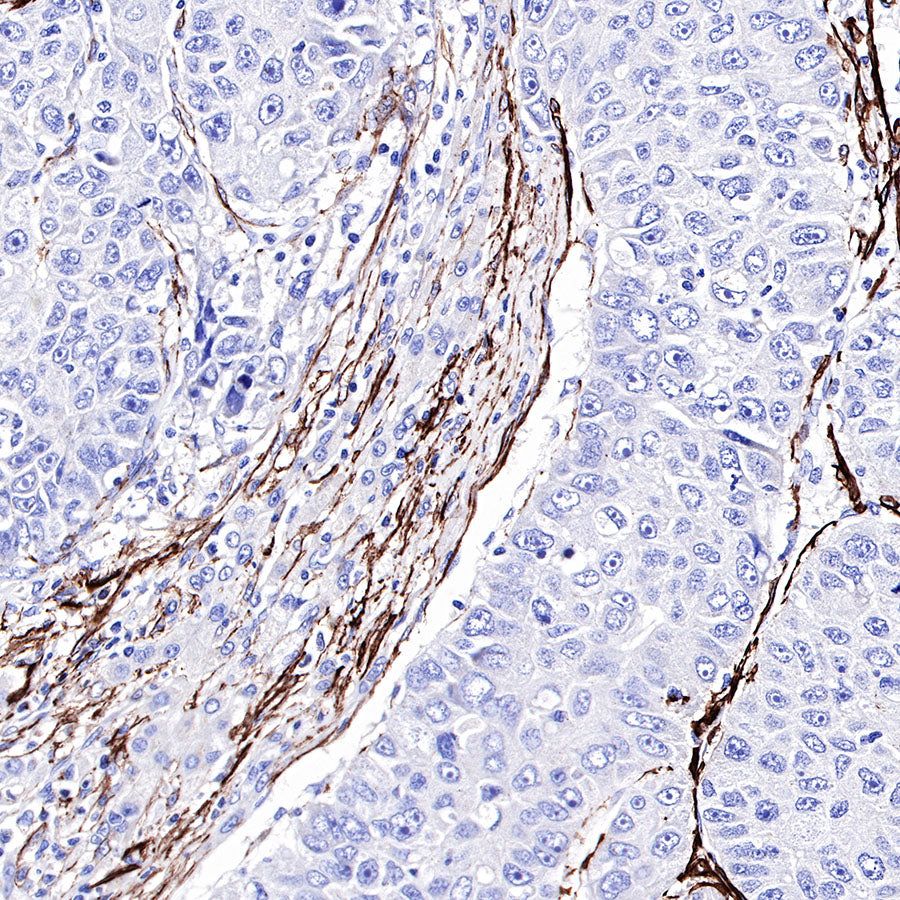

Immunohistochemistry